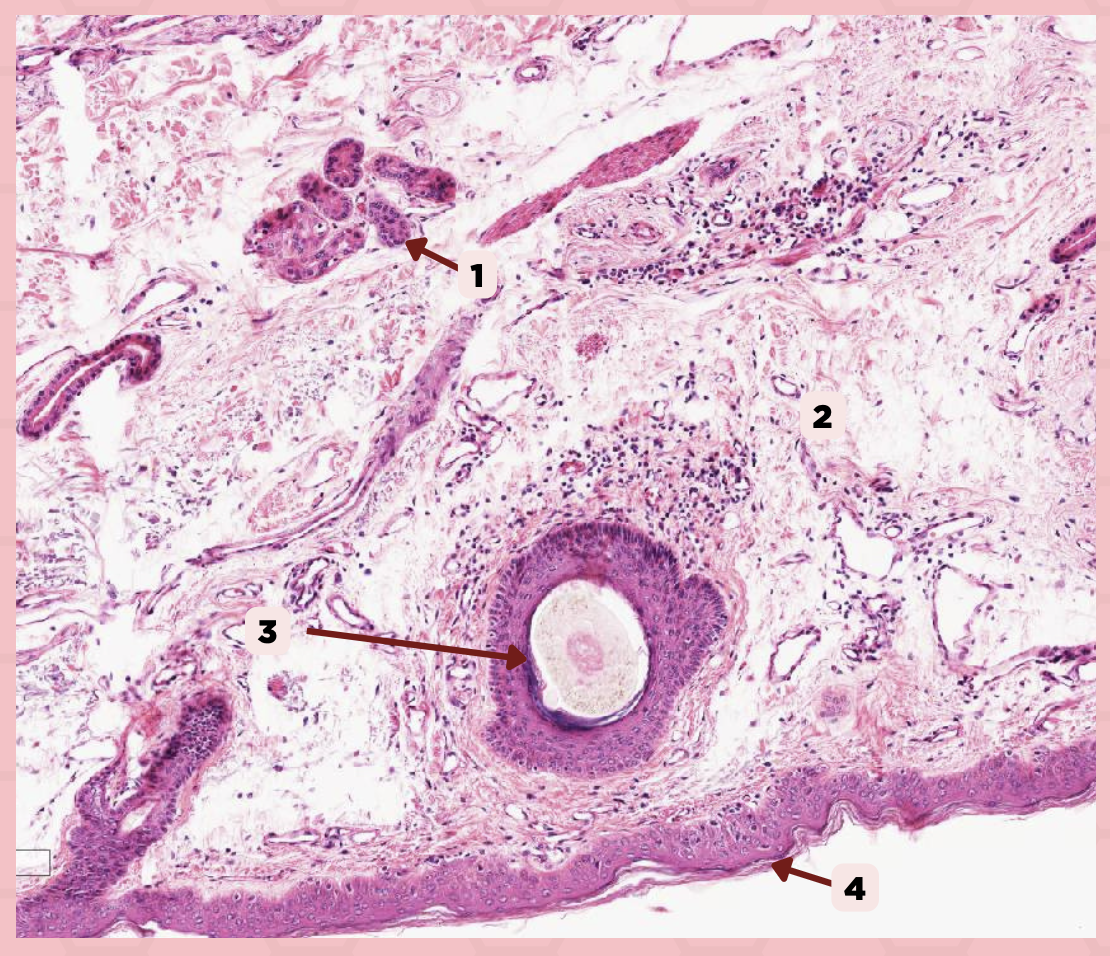

Lip

What specimen is being showed in the picture?

Epidermis

Identify the structure labeled as 1.

Dermis

Identify the structure labeled as 2.

Arrector Pilli Muscle

Identify the structure labeled as 3.

Hair Follicle

Identify the structure labeled as 4.

Sebaceous Glands

Identify the structure labeled as 5.

Lip

What is the specimen showed in the picture?

Epidermis

Identify the structure labeled as 1.

Dermis

Identify the structure labeled as 2.

Arrector Pilli Muscle

Identify the structure labeled as 3.

Hair Follicle

Identify the structure labeled as 4.

Sebaceous Glands

Identify the structure labeled as 5.